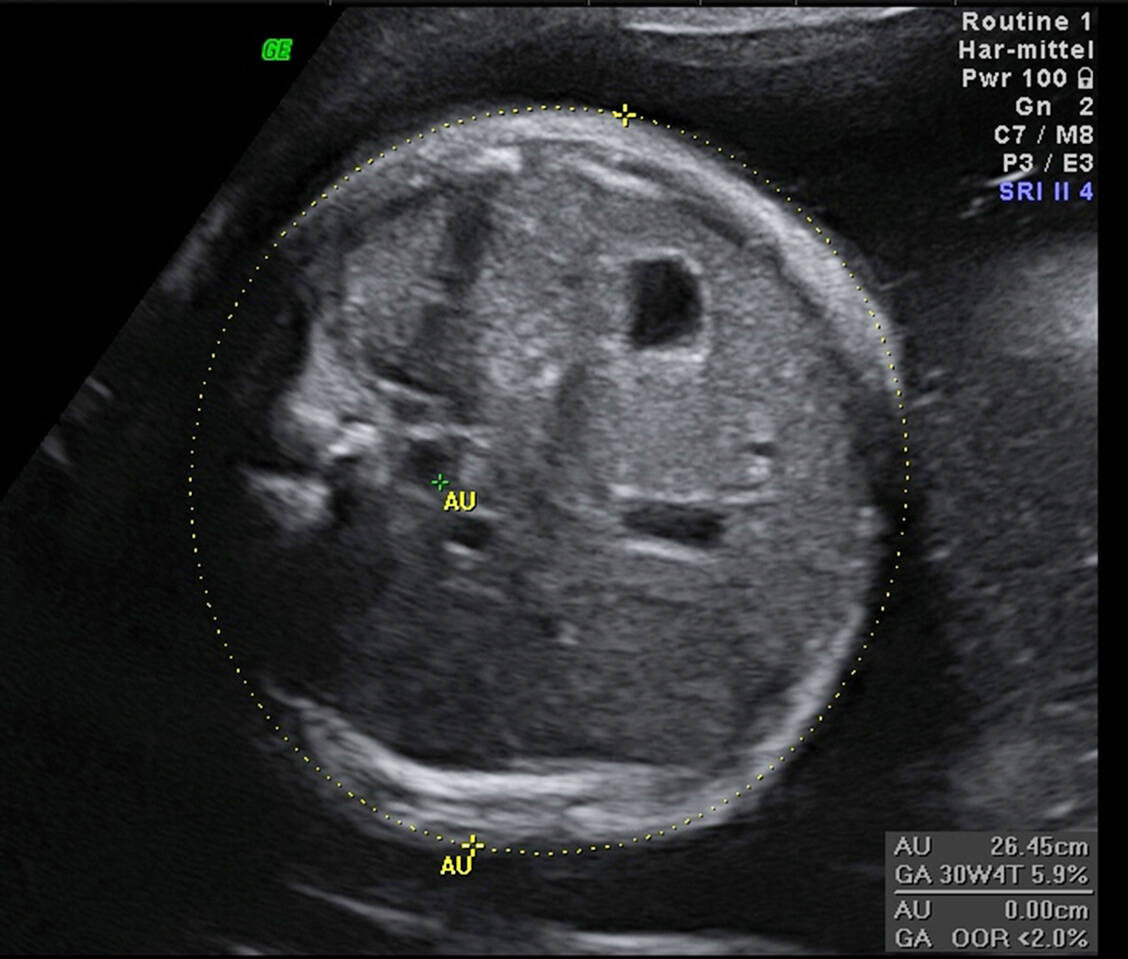

MODY-Formen werden autosomal-dominant vererbt, das heißt, 50 Prozent der Nachkommen weisen die Mutation geschlechtsunabhängig auf. Der häufige GCK-MODY (MODY 2) wird außerhalb der Schwangerschaft ohne Medikation geführt, die Prognose ist gut, es kommt fast nie zu Folgekomplikationen. Bei diesen Schwangeren, die normgewichtig sind und meist nur persistierend erhöhte Nüchternglukosewerte haben, wird erst bei einem fetalen Abdominalumfang (AU) über der 75. Perzentile und dysproportionalem Wachstum mit Insulin therapiert.

Blutglukoseselbstmessungen durch die Schwangere werden anfangs morgens nüchtern und nach den Hauptmahlzeiten durchgeführt. Die in Tabelle 3 aufgeführten Einstellungsziele für die ersten eine bis zwei Wochen der GDM-Therapie werden modifiziert, wenn niedrigere Ziele bei einem fetalen AU > 75. Perzentile erreicht werden sollen und gleichzeitig Hinweise für ein dysproportionales Wachstum, zum Beispiel eine Kopf-/Abdominalumfang-, (KU/AU)-Ratio < 10. Perzentile gegeben sind. Eine entsprechende Anpassung ist auch nötig, wenn höhere Ziele bei mütterlicher Hypoglykämieneigung unter Insulintherapie (sehr selten) angestrebt werden müssen.

Die fetale Überwachung ist von zusätzlichen Risikofaktoren und dem Schweregrad der mütterlichen Hyperglykämie abhängig. Neben den üblichen Ultraschallkontrollen werden zusätzlich ab der 24. SSW alle zwei bis vier Wochen (je nach Ausgangsbefund und Verlauf der Blutglukoseeinstellung) fetale Ultraschallbiometrien mit einer Beurteilung der Zunahme des Abdominalumfangs und der Proportionalität durchgeführt.